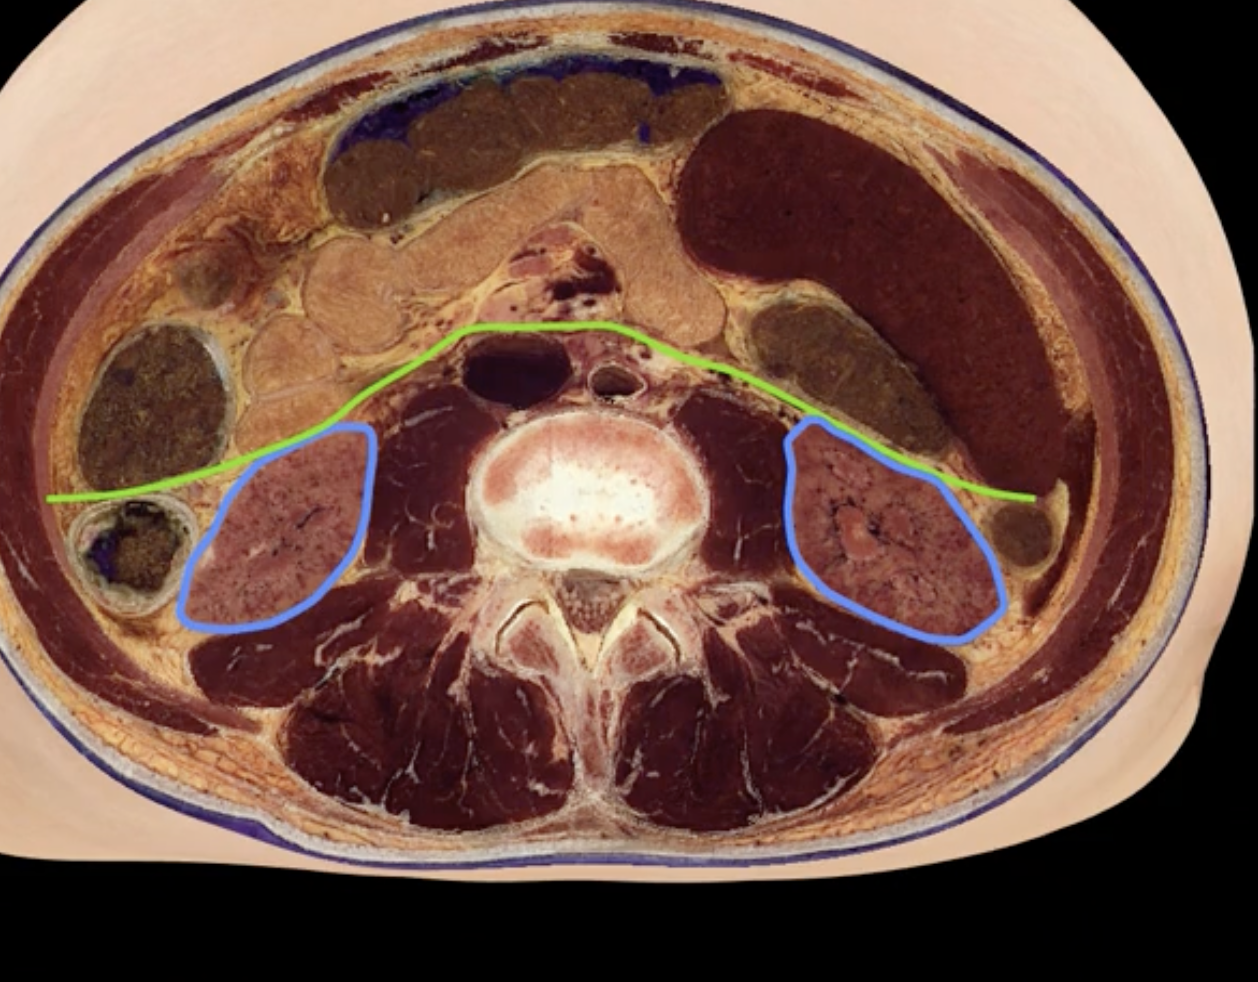

green: peritoneum

blue: kidneys

green and blue are showing that the kidneys are retroperitoneal

posterior abdominal wall